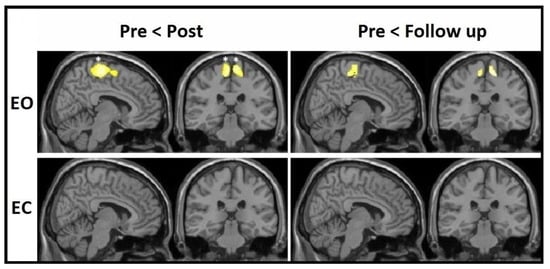

From subsequent within-group VBM analyses for both groups, it was evident that the increases in the sensory-motor cortices bilaterally were visible for the EO group only at the corrected level, with no significant effects in the EC group whatsoever (Figure 3). These corrected effects were present at the post-test, whereas a drop in both significance and cluster size could be seen at the follow-up. MNI coordinates, cluster sizes, and significance values of these changes are all listed in Table 4.

Figure 3.

VBM-observed GM increments—within-group effects from pre-test to post-test and from pre-test to follow-up for both EO and EC groups; * FWE-corrected.